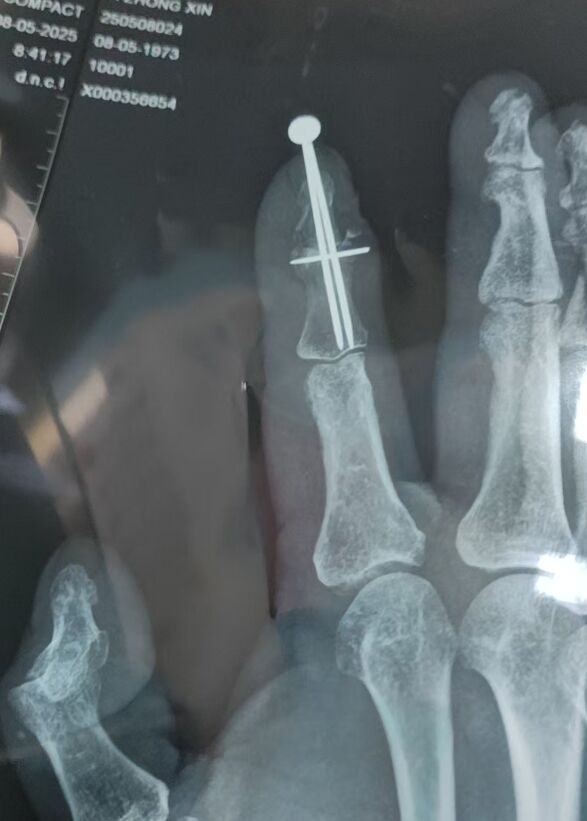

门诊经常遇到特殊病例

在韩国做的手术

未住院,手术费用折合人民币大概7万

这个克氏针尾帽,让我眼前一亮

还是内六角螺丝固定的

从X线片看,应该是做的DIP关节融合术

里边居然是3枚克氏针

本帖最后由 zhangwenlong 于 2025-6-2 08:47 编辑

从外观像看,以为这个尾帽仅是做完美外观,防止克氏针针尾划伤身体,或者防止别勾带出来的目的

从X线片看,这个尾帽可能有更多的目的和意义

比如:不平行置钉,针尾链接,起到提高弹性把持力作用;

再或者,有没有可能是绞锁髓内钉的用法呢

看3枚克氏针交汇处,特像绞锁髓内钉